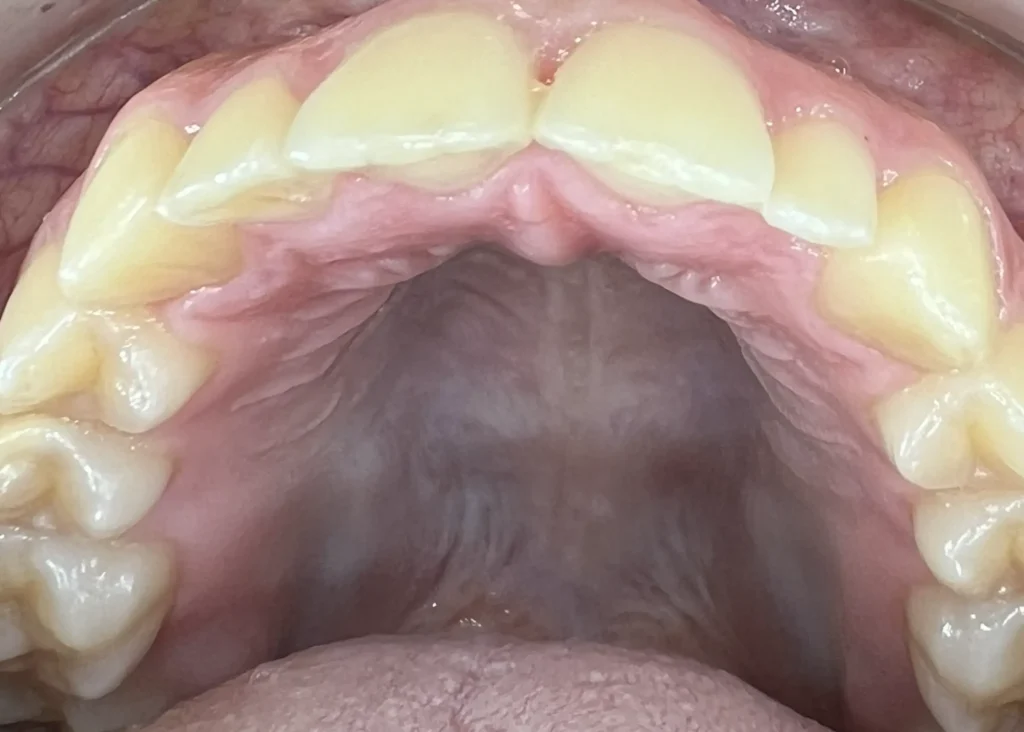

La ortodoncia invisible o Invisalign Ferrol es una técnica de ortodoncia basada en alineadores transparentes, mediante la que se pueden mover y recolocar las piezas dentales tras realizar una predicción a través de un sofisticado software de tecnología 3D que escanea la boca del paciente.

Casos clínicos de ortodoncia en CDPA